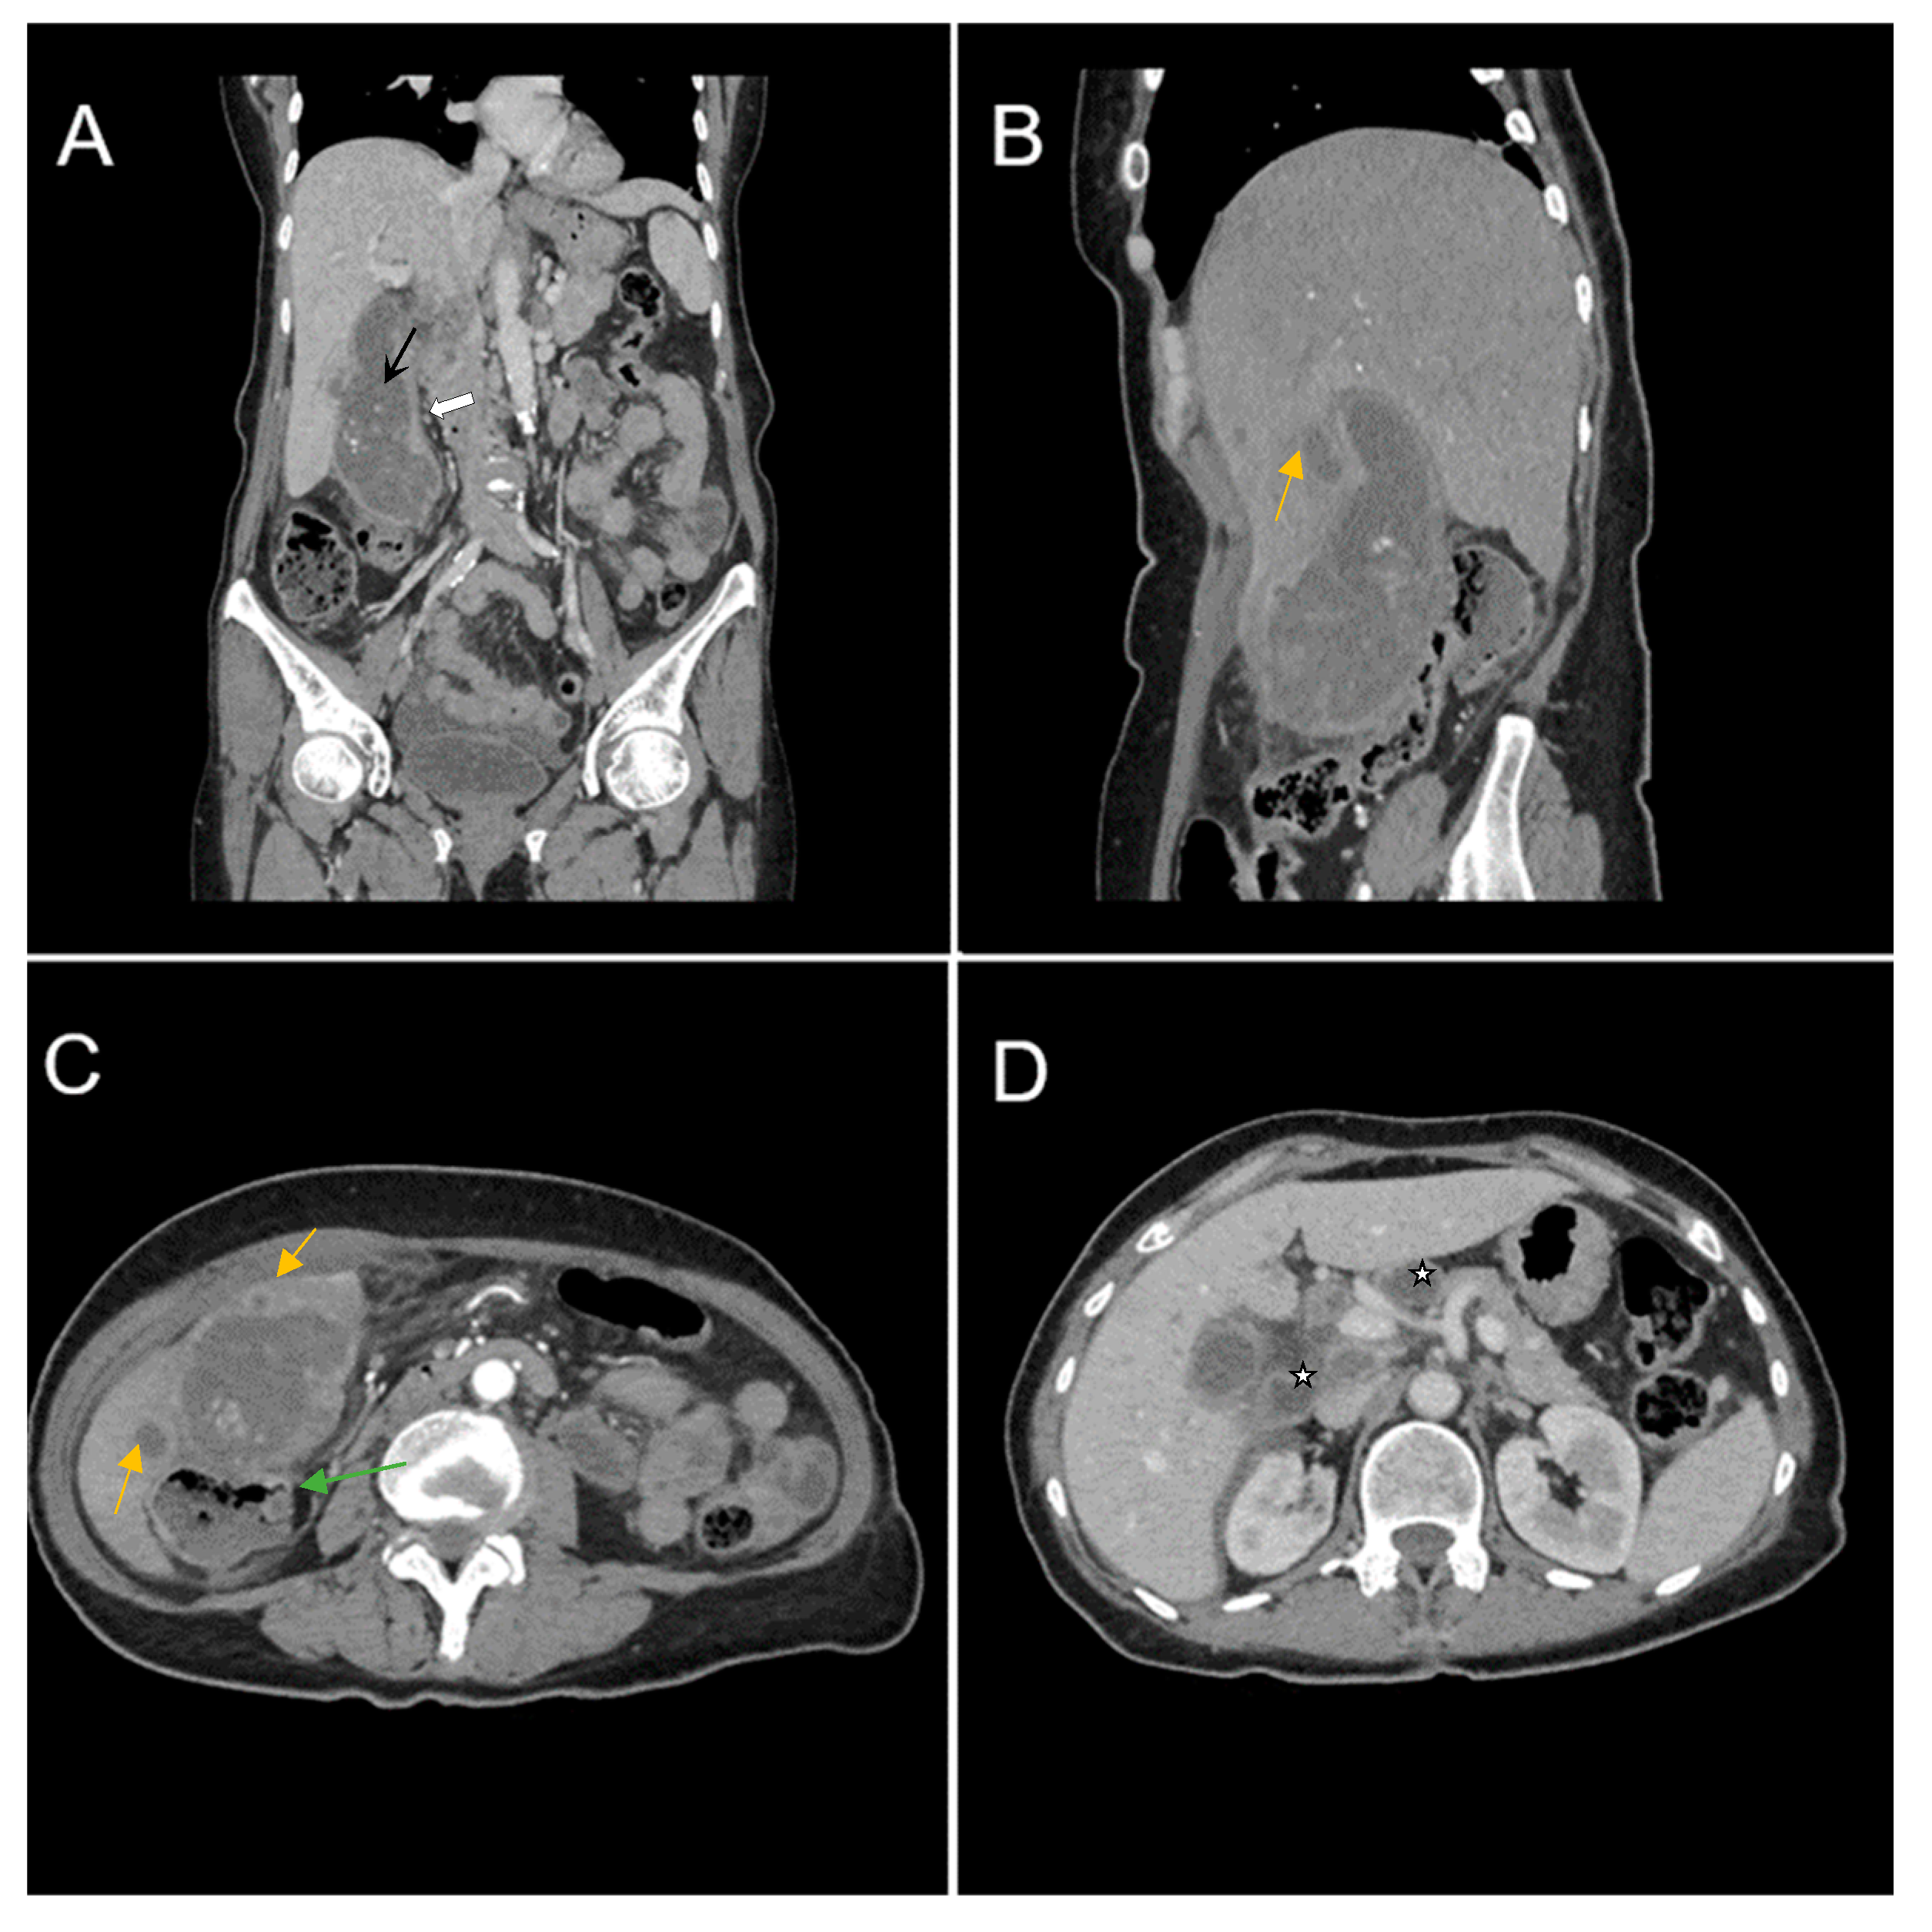

A 67-year-old female patient with a past medical history of hypertension and autoimmune thyroiditis presented to the Emergency Department with abdominal pain accompanied by nausea and weight loss. Physical examinations revealed abdominal tenderness with a palpable mass in the right hypochondrium. Blood sample demonstrated elevated inflammatory markers, hypochromic microcytic anemia, hepatic cytolysis and increased levels of CEA (12.5 ng/mL) and CA 19-9 (51 U/mL). Contrast-enhanced emergency CT (Figure 9) showed a large mass with heterogeneous enhancement, measuring 94/57 mm, that partially replaced the gallbladder and invaded the liver (segment IVb), pyloric antrum and duodenum II. Bulky celiac and mesenteric lymphadenopathies with areas of necrosis, measuring up to 27/25 mm were present.

Figure 9. Multiplanar sections of contrast-enhanced CT acquisitions richly illustrating gallbladder carcinoma. (AD). A large, inhomogeneous pseudonodular mass with heterogeneous contrast enhancement, with invasion in the adjacent liver, pyloric antrum and duodenum II (white arrows). (A) Lymphatic metastases; with compressive effect on the inferior vena cava and right renal artery and vein (blue arrow).